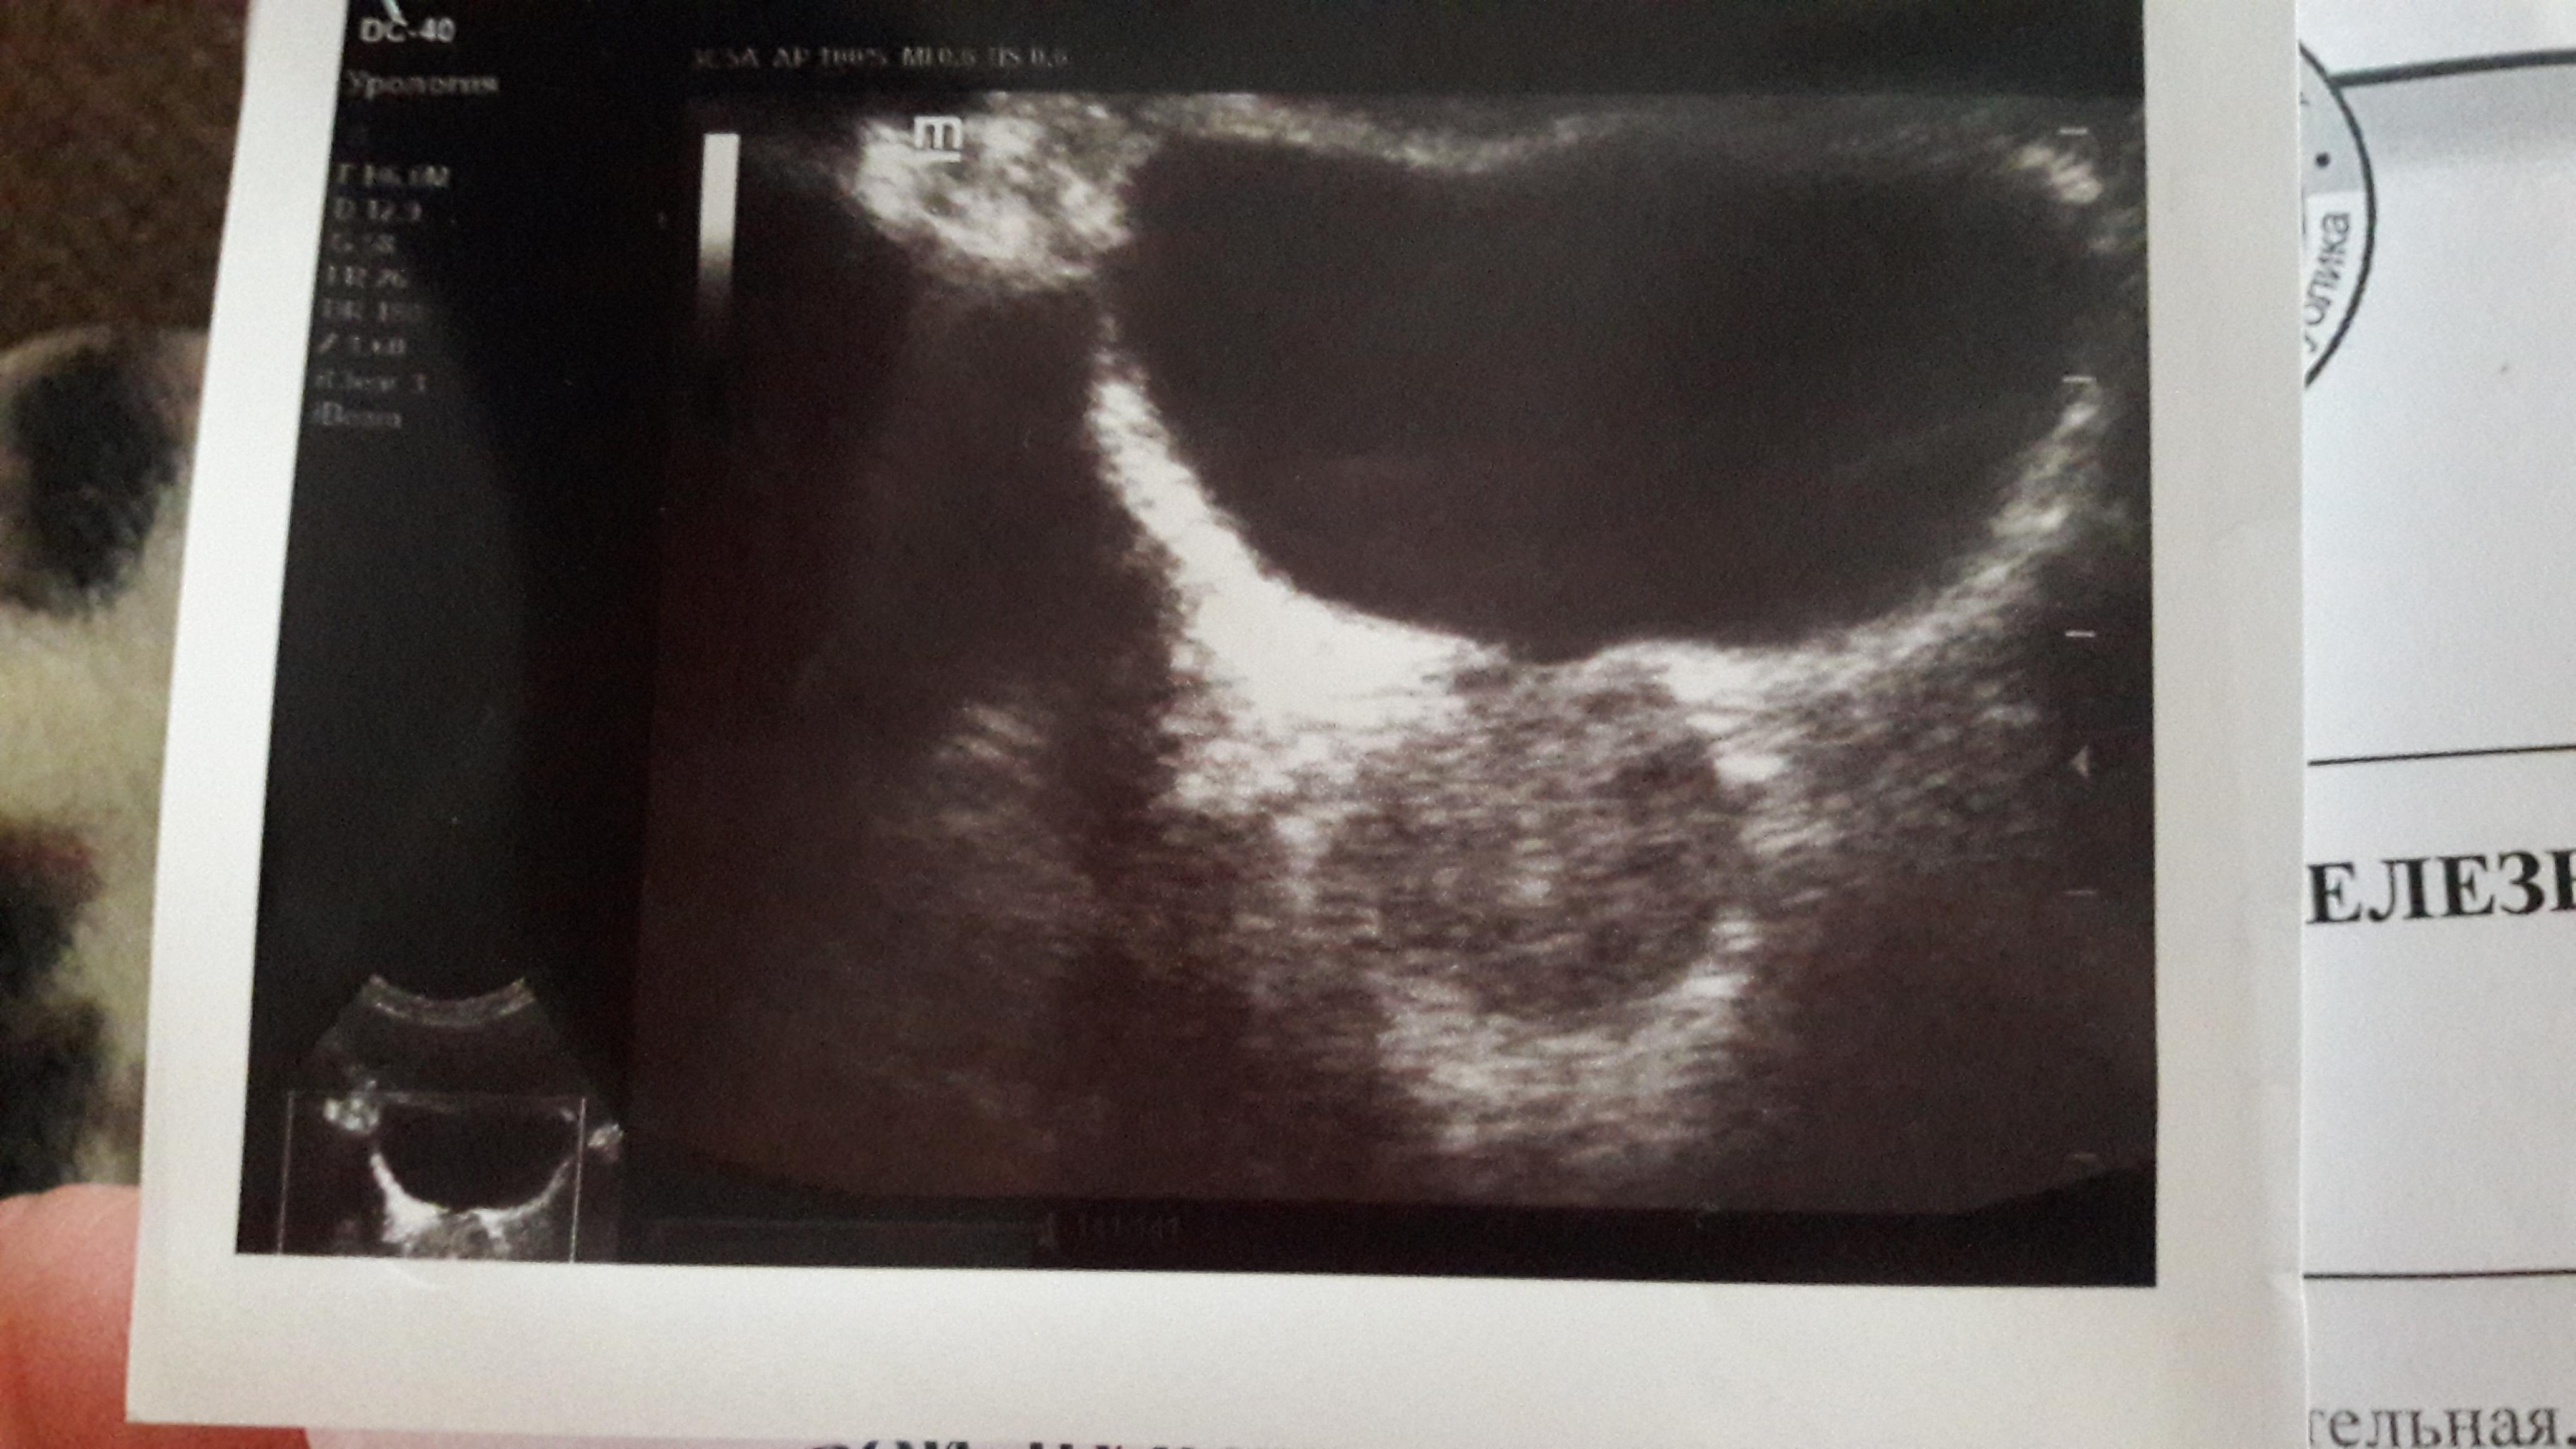

Размеры 39*34*37 мм,обьём 25,5 см2.Контуры ровные.Капсула не утолщена.Эхогенность железы несколько пониженная,структура с кальцинатом в правой доле.Внутрипузырный компонент 0 мм.

Здравствуйте! Результаты УЗИ надо трактовать в сочетании с клинической картиной. В данном случае можно предположить имевший место воспалительный и\или застойный процесс. В организации персонифицированной консультации мы готовы Вам помочь на базе наших клиник .